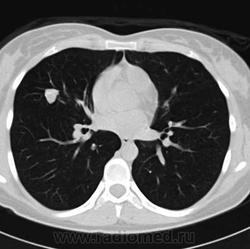

Пациентка А., 1988 года рождения. В возрасте 13 лет в течение года наблюдалась по поводу железодефицитной анемии, при контрольном обследовании была выявлена гигантская опухоль нижней трети желудка. В стационаре по месту жительства выполнена резекция желудка по Бильрот-1. При гистологическом исследовании диагностирована лейомиобластома с местнодеструирующим характером роста. Через 6 лет отмечено прогрессирование опухолевого процесса в желудке и больную направили в РОНЦ им. Н.Н.Блохина. При гастроскопии в оставшейся части желудка выявлены два подслизистых образования, располагающиеся в субкардиальном отделе и в верхней трети тела по малой кривизне и задней стенке, диаметром 1,0 см и 0,5 см. При гистологическом исследовании биоптата слизистой выявлена веретеноклеточная неэпителиальная опухоль желудка – ГИСО. При рентгенологическом исследовании органов грудной клетки (рис. 1,А-В)в легких с обеих сторон определялись множественные очаги и фокусы уплотнения от 0,4 см до 3,6см, неоднородной структуры с четкими контурами, с участками обызвествления по периферии.

рис.1Б. КТ органов грудной клетки в горизонтальной проекции.

рис.1В. То же, что на рис. Б (другой уровень).

Для уточнения природы имеющихся изменений выполнено торакоскопическое прецизионное удаление узлового образования верхней доли правого легкого. При гистологическом исследовании получен материал, соответствующий хондроматозной гамартоме с признаками оссификации. По данным КТ брюшной полости также выявлялись очаги в печени в диаметре до 1,4 см. Больная наблюдалась в течение 2х лет, затем было диагностировано прогрессирование заболевания в виде роста образований в желудке, появления новых очагов в печени и в легких по данным КТ (рис. 1- Г, Д.Е).

рис.1Д. КТ органов грудной клетки в горизонтальной проекции через 2 года.

рис.1Е. То же, что на рис. Д (другой уровень).